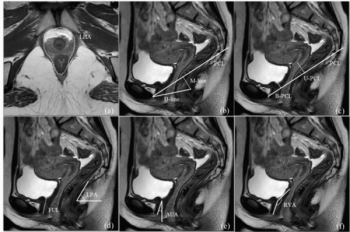

Researchers found that the combination of a retrovesicourethral angle, functional urethral length, and bladder funnel on MRI exams in primiparous women had a 94.7 percent AUC for predicting postpartum stress urinary incontinence (SUI).